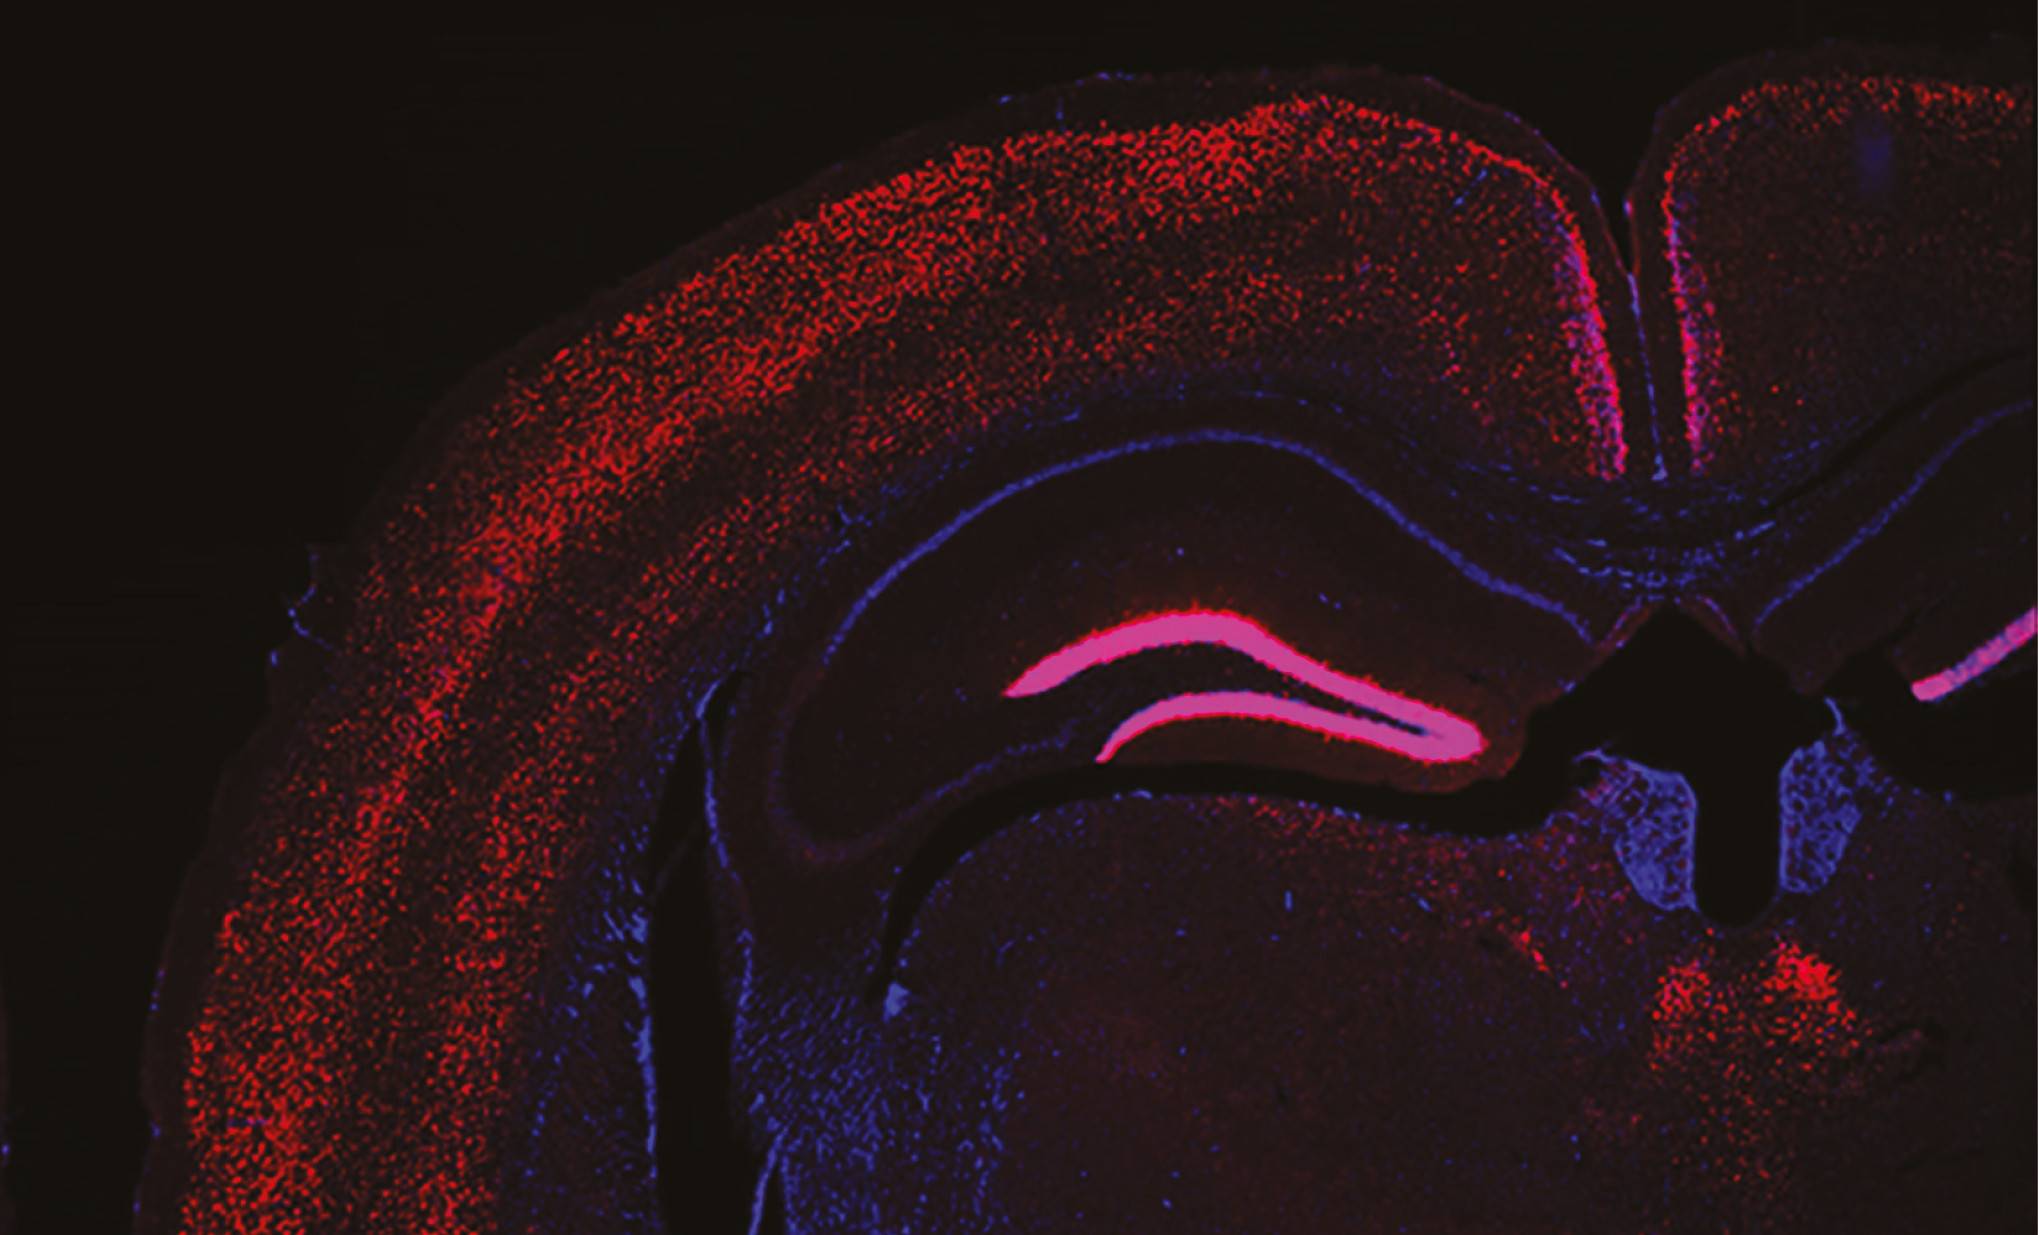

cervell marcat síndrome leigh ES

Mediante técnicas avanzadas de imagen, electrofisiológicas y genéticas, el equipo descubrió que las neuronas gabaérgicas del GPe son particularmente vulnerables a la disfunción mitocondrial, lo que conduce a su degeneración generalizada. Como estas neuronas son las encargadas de mantener bajo control la actividad del STN, su pérdida hace que este núcleo se vuelva hiperactivo, lo que provoca crisis epilépticas recurrentes en los animales.En cambio, cuando el equipo restauró la función mitocondrial en el GPe, las crisis casi desaparecieron. Los ratones vivieron más tiempo y mostraron una mejora notable de la función neurológica.